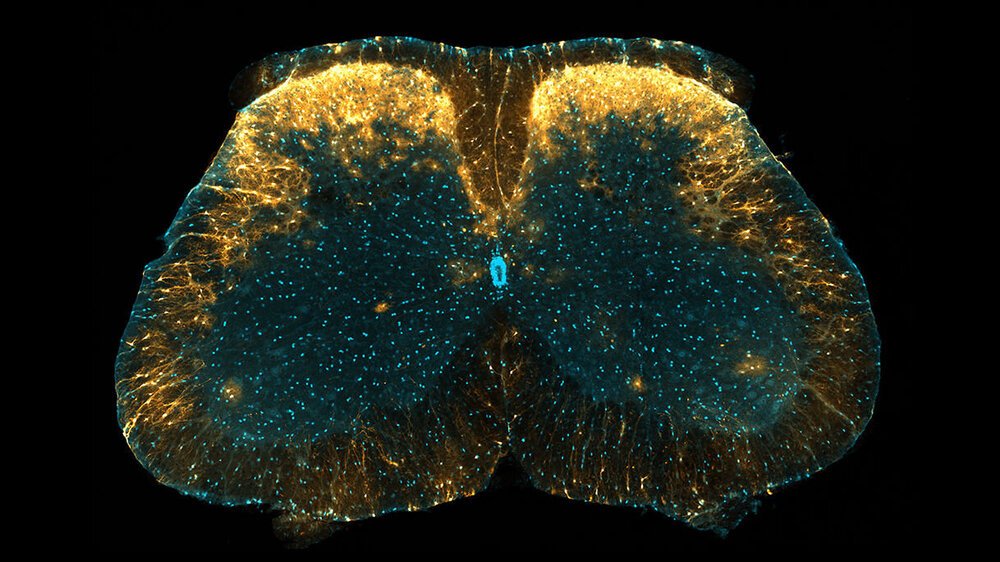

در میان انواع مختلف سلولهای گلیا ، آستروسیتها بیشتر در سیستم عصبی مرکزی دیده می شوند ، اما بر خلاف نورونها در قسمتهای مختلف مغز ، محققان هنوز نتوانسته اند درک درستی از طبقه بندی آستروسیتها که دارای ویژگیهای مشخص هستند ، بدست آورند.

این تیم به سرپرستی محقق دانشگاه کیوتو ، ماکوتو تسودا ، گروه منحصر به فردی از آستروسیت های ستون فقرات را کشف کردند که نقش مهمی در تولید حساسیت به درد دارند.

این گروه از آستروسیت ها که در دو لایه خارجی ماده خاکستری مغز نزدیک پشت نخاع وجود دارد ، در مناطقی قرار دارند که اطلاعات حسی عمومی مانند فشار ، درد و گرما را از بدن به مغز منتقل می کنند.